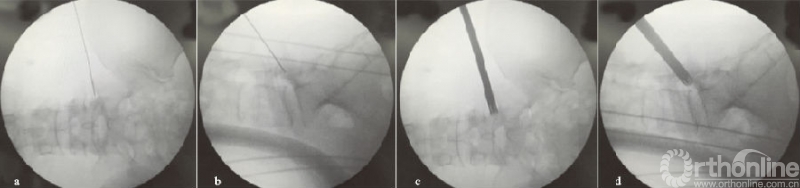

(a)(b)L4/5节段向上游离型突出穿刺置管透视图,其中(a-b)为一级导杆定位图;(c)(d)工作通道放置图;(e-h)L4/5节段向下游离型突出穿刺置管透视图,其中(e-f)为保护套管下环锯行FP图;(g)(h)工作通道放置图

图4 L4/5节段游离型突出穿刺置管图